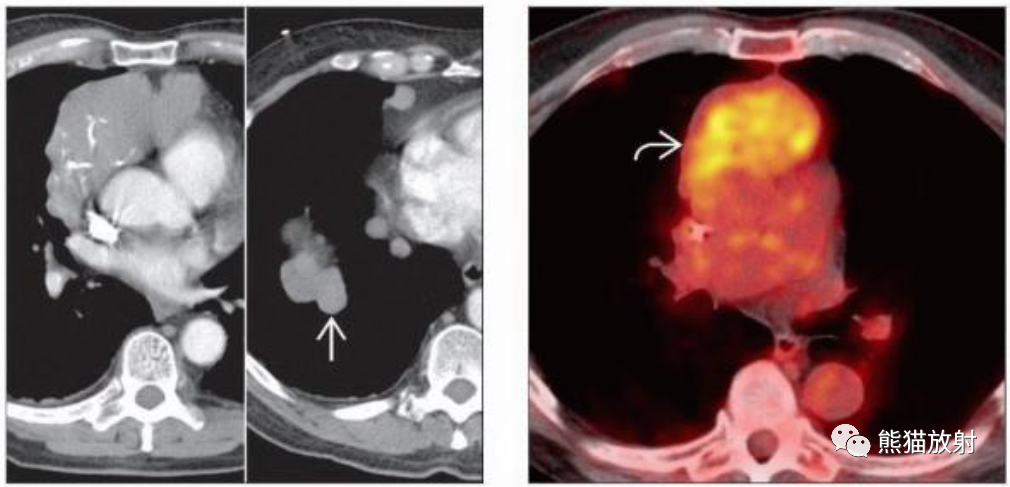

(左) 胸腺瘤,增强CT显示右前纵隔球形肿块,由于坏死中心呈低密度。与邻近升主动脉分界清晰(箭)。

(左) 侵袭性胸腺瘤。CT增强显示巨大右前纵隔分叶状肿块伴钙化,同侧膈肌和纵隔胸膜多发转移,提示IVa期。

(右) 同一病人的PET/CT显示病灶FDG代谢增高 (SUV为4.5)。虽然PET/CT在胸腺瘤评估中的作用尚未明确,但它可能有助于明确部分病例的转移灶。